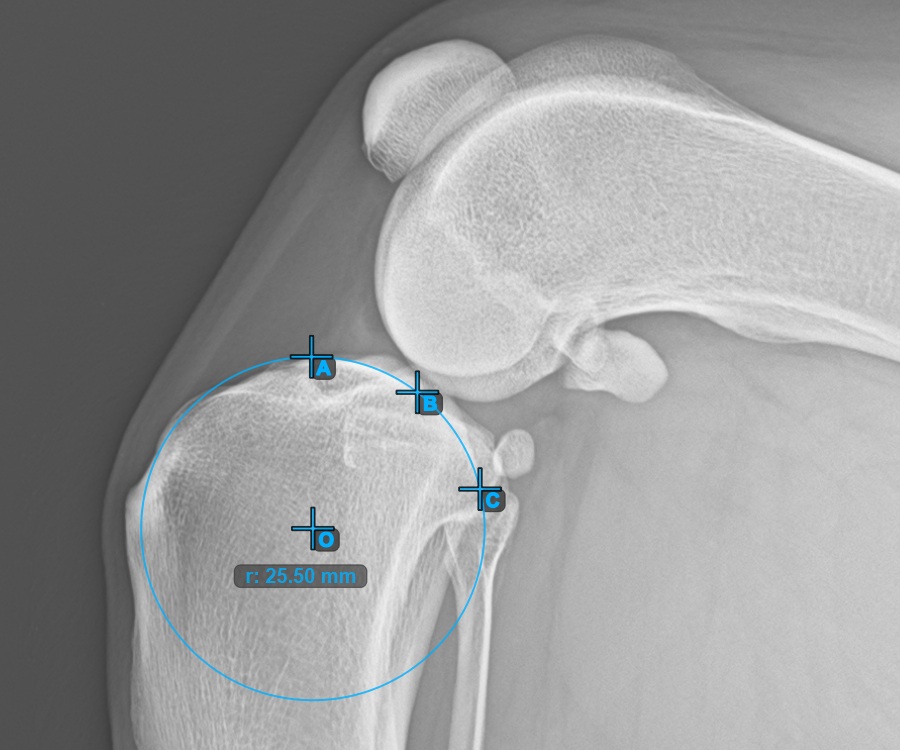

Kezdje el a mérést a három pont megjelölésével a Condylus Medialis Tibialis-on.

Jelölje meg a három pontot a tibia fő condylusán (Medialis Tibialis). A sorrendtől függetlenül ügyeljen arra, hogy megjelölje a legfelső pontot, a legalacsonyabb pontot és a Medialis Tibialis középpontját. A három pont alapján a rendszer automatikusan létrehoz egy kört.

A lenti kép a Condylus Medialis Tibialis-on elhelyezett három pont tipikus elhelyezkedését ábrázolja.